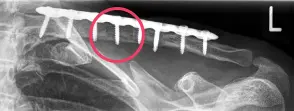

- Der Marknagel kann – je nach knöcherner Heilung – nach frühestens 3 Monaten wieder entfernt werden. Die Platten, welche doch oftmals etwas auftragen und stören, werden in aller Regel frühestens nach einem Jahr entfernt. Eine zu frühe Metallentfernung birgt das Risiko einer Re-Fraktur (siehe Abbildung), d.h. eines erneuten Schlüsselbeinbruchs.

Abbildung: Zweite Episode einer Re-Fraktur bei einer jungen Patientin. Daher Revision mit langer Platte und zudem Einsetzen eines Beckenkammspans (rot markiert) post-OP und das Ausheilungsergebnis 1 Jahr nach der OP